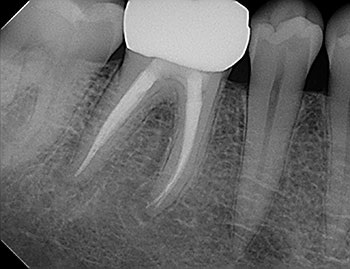

Fig. 1: Preoperative PA.

Tooth #30 had a diagnosis of previous root canal treatment with symptomatic apical periodontitis. The mesial root had a classic J-shaped radiographic lesion and a narrow probing defect from the buccal furcation to the root apex. No crack could be seen on what little root surface was visible. The likelihood of VRF, or the possibility of a failing root canal with a chronic apical abscess, were discussed. The latter could be treatable. The plan was to attempt re-treatment after internal inspection for a possible VRF.